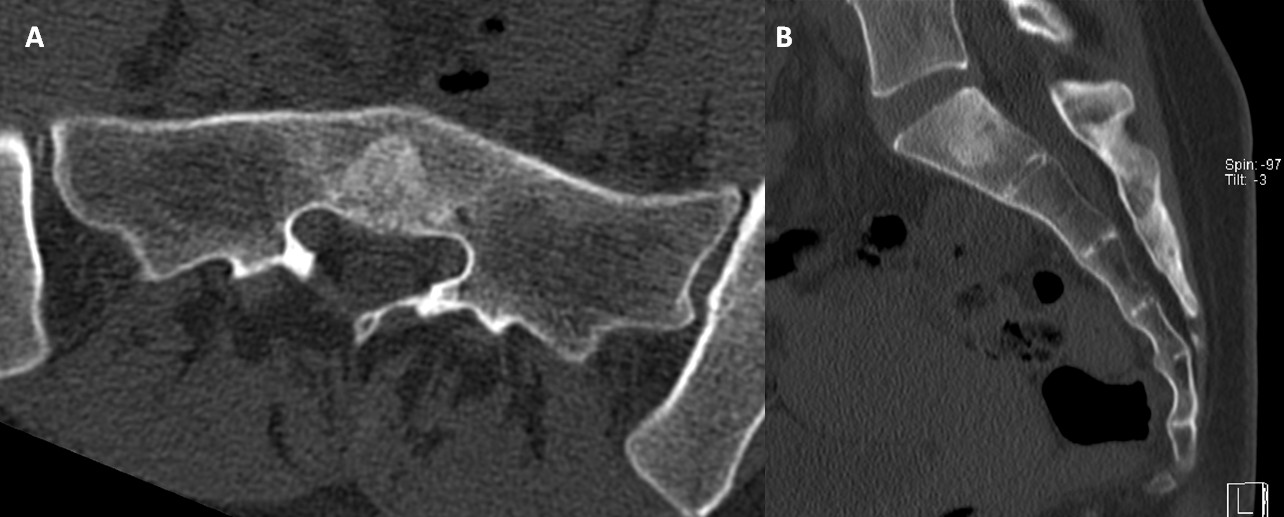

Subsequent CT of the lumbosacral spine (Fig.2) demonstrated a mild osteosclerotic lesion with poorly defined margins with preservation of the trabecular bone pattern. No radiological signs of aggressiveness, such as bone destruction or soft tissue involvement were observed.

Figure 2: Axial (A) and Sagittal (B) CT images of the lumbosacral spine show a mild osteosclerotic lesion in the midline of the S1 vertebral body, with poorly defined margins and preservation of the trabecular bone pattern. No evidence of bone destruction or soft tissue involvement is observed.